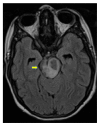

We report a case of a Somali refugee who presented in the second trimester of her first pregnancy with a four-week history of gradual right-sided sensomotoric hemisyndrome including facial palsy and left-sided paresis of the oculomotorius nerve causing drooping of the left eyelid and double vision. Cranial magnetic resonance imaging revealed a solitary brainstem lesion. Upon detection of hilar lymphadenopathy on chest X-ray (CXR), the diagnosis of disseminated tuberculosis with involvement of the central nervous system was confirmed by PCR and treatment induced with rifampicin, isoniazid, pyrazinamide, and ethambutol. The patient had a steady neurological improvement and a favorable pregnancy outcome.